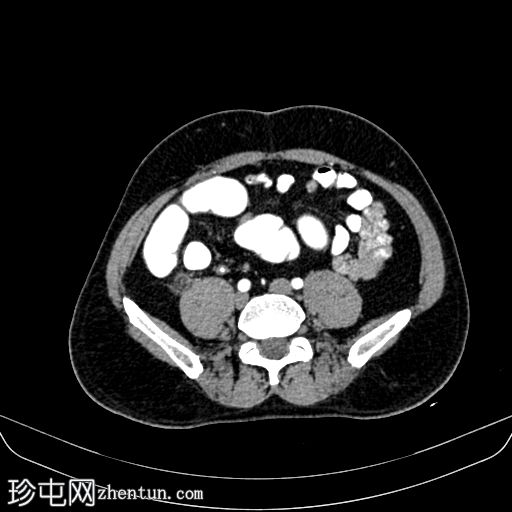

轴位增强扫描

门静脉期

门静脉期,可见一持续存在的脂肪密度影,周围环绕高密度环;周围脂肪条索状改变,无脓肿形成,邻近结肠无憩室,盲肠壁正常。无阑尾炎,无淋巴结肿大,无游离气体或液体。